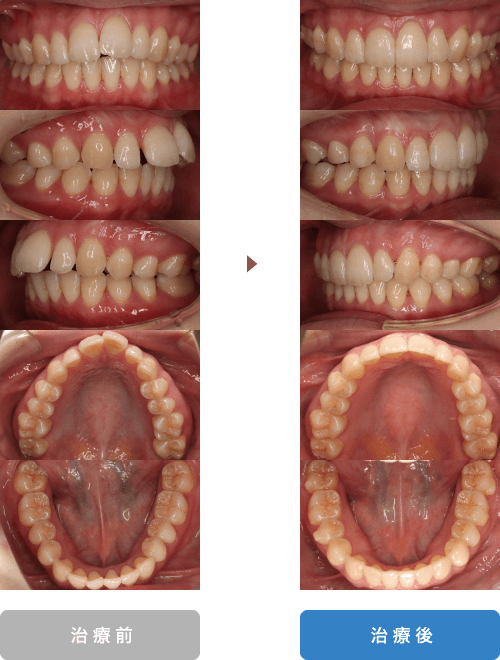

| 主訴 | 上の前歯が内側に入っている |

|---|---|

| 年齢 | 23歳 |

| 治療期間 | 1年7ヶ月 |

| 通院回数 | 24回 |

| 治療内容 | セラミックブラケットとホワイトワイヤーにより治療を行いました。 |

| 抜歯部位 | 非抜歯 |

| 治療費 | 約84万円(税込:治療当時税率8%) ※処置料、保定料も含む |

| リスク、副作用 | 骨癒着などにより歯が動かない場合や、 矯正治療によって歯肉退縮する可能性があります。 |

| 担当医 | 長島歯科・矯正歯科 長島雄吾 |